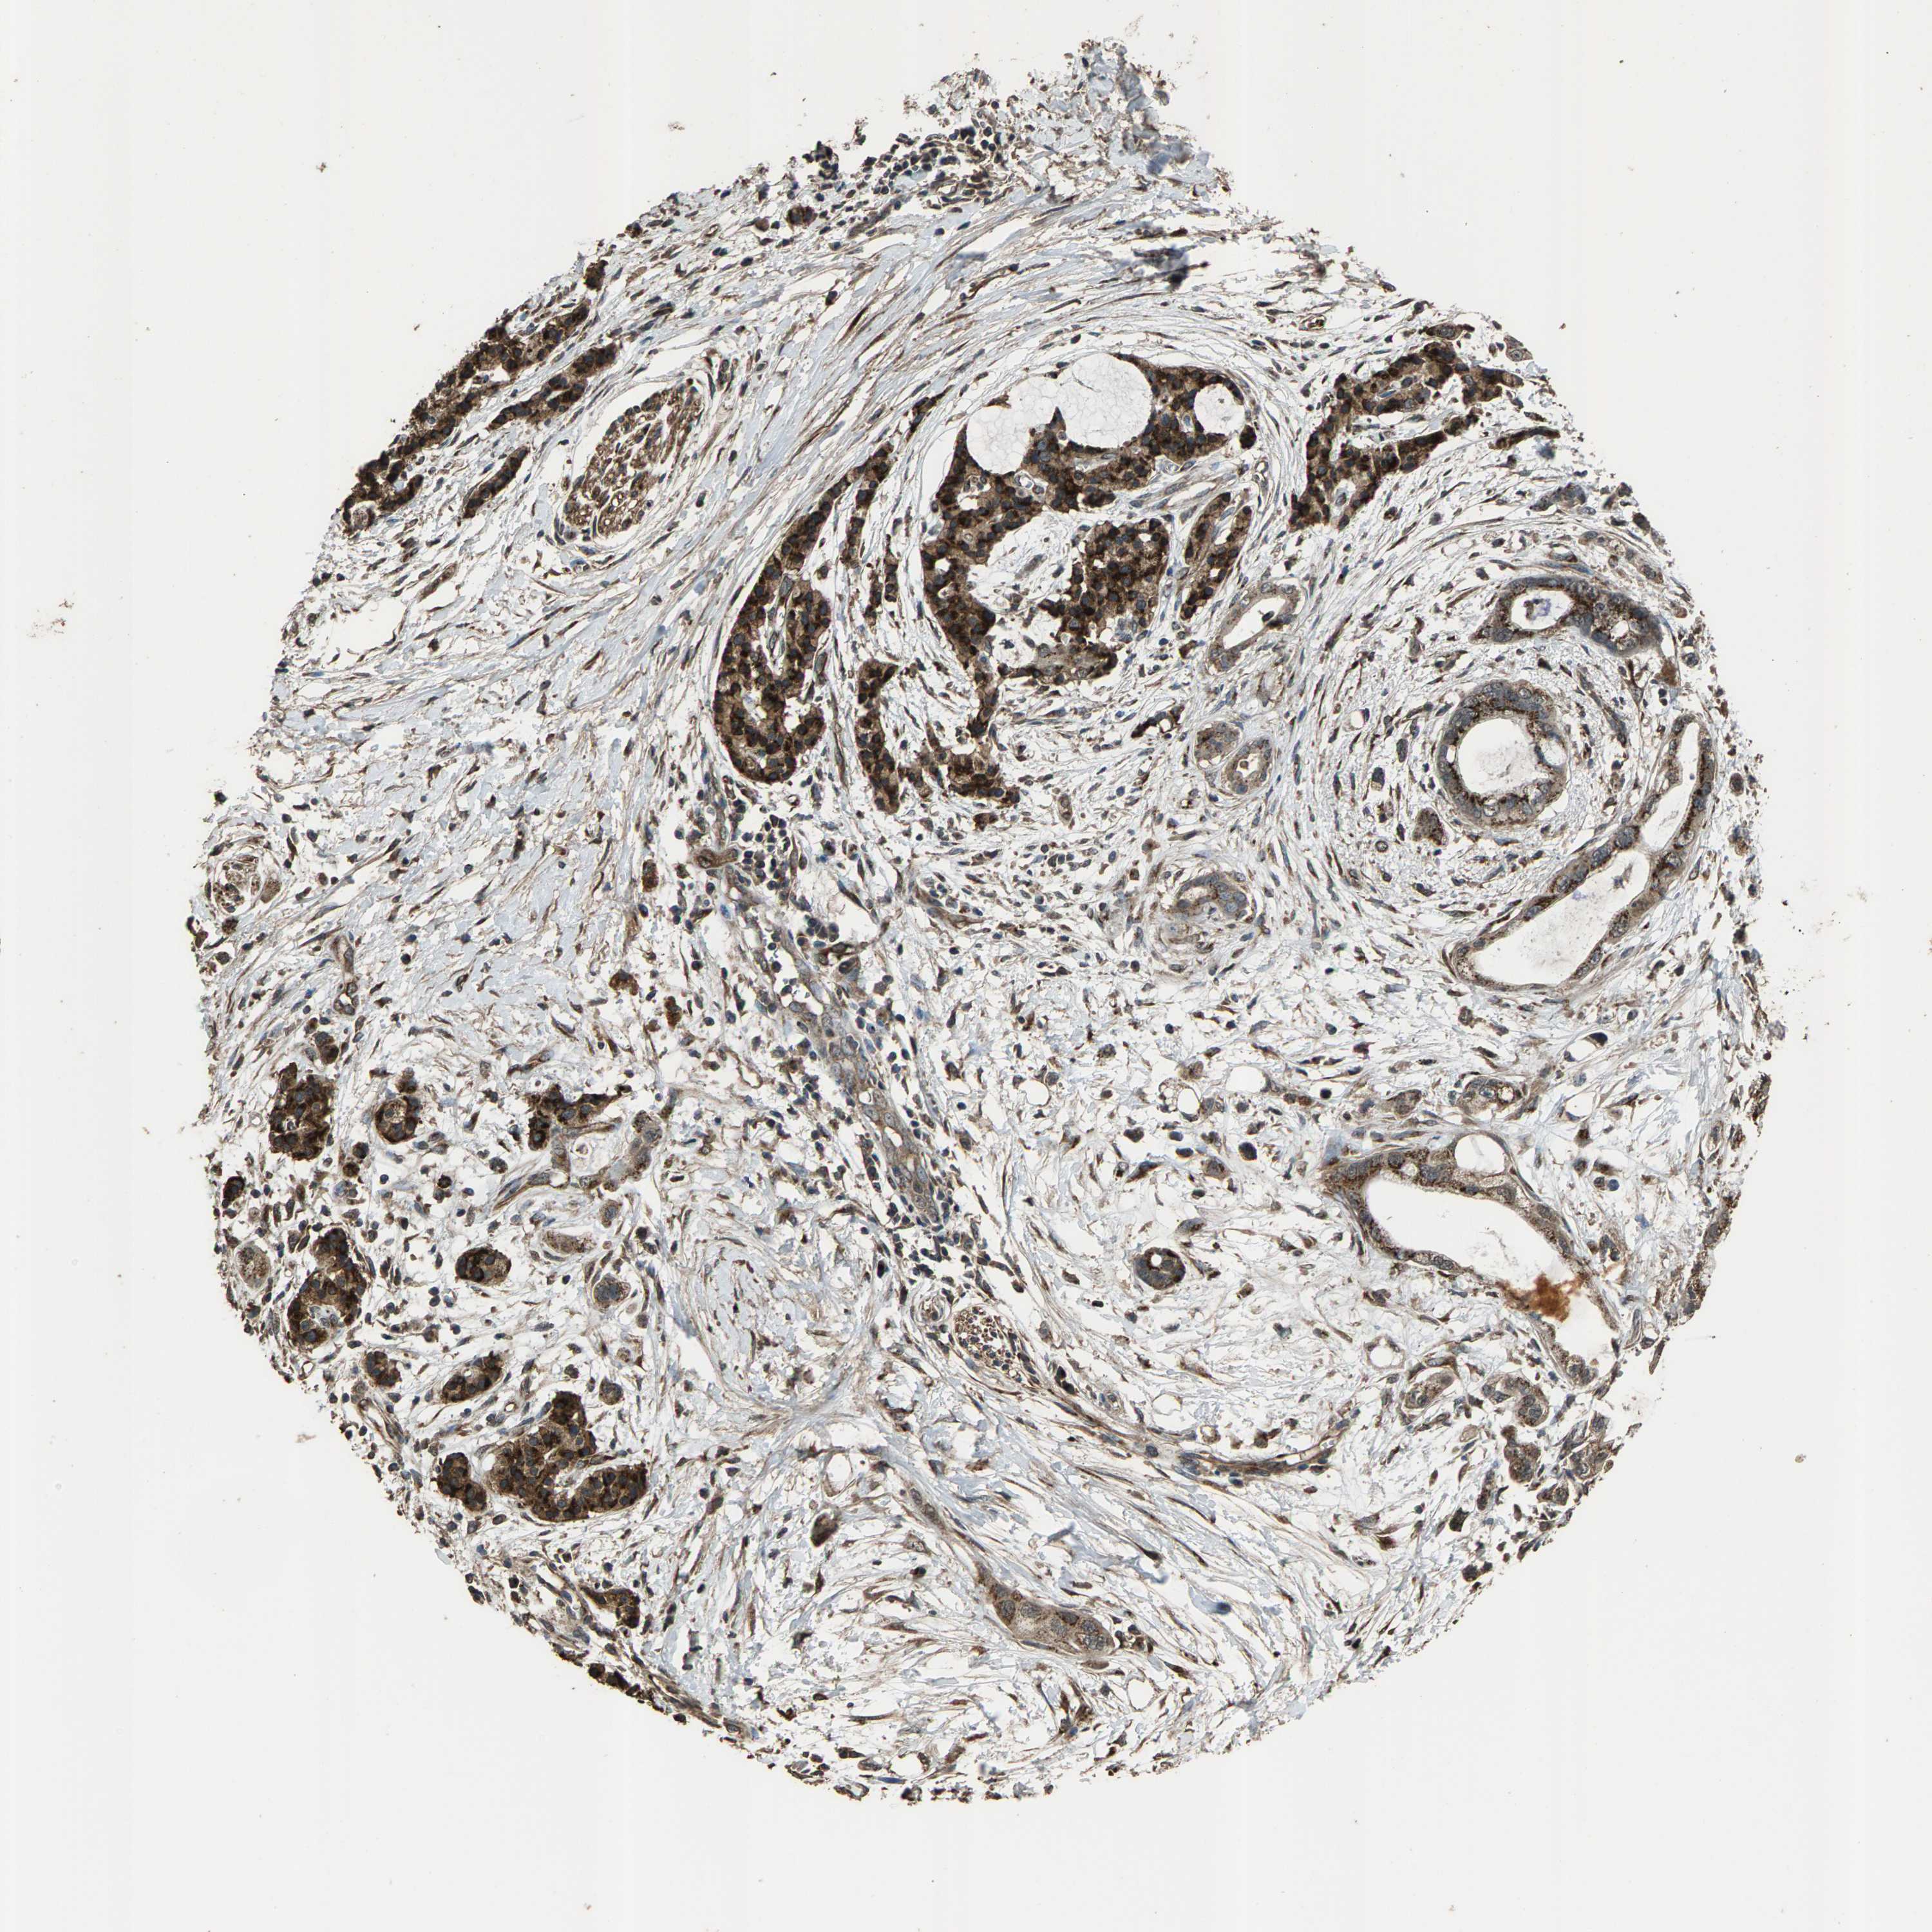

PANCREATIC CANCER - Protein expressioni

A mouse-over function shows sample information and annotation data. Click on an image to view it in a full screen mode. Samples can be filtered based on level of antibody staining by selecting one or several of the following categories: high, medium, low and not detected. The assay and annotation is described here.

Note that samples used for immunohistochemistry by the Human Protein Atlas do not correspond to samples in the TCGA dataset.

Antibody stainingi

Antibody staining in the annotated cell types in the current human tissue is reported as not detected, low, medium, or high, based on conventional immunohistochemistry profiling in selected tissues. This score is based on the combination of the staining intensity and fraction of stained cells.

Each image is clickable and will lead to virtual microscopy that enables deeper exploration of all samples and also displays staining intensity scores, fraction scores and subcellular localization as well as patient and tissue information for each sample.

Antibody HPA021374

Antibody HPA023161

Antibody HPA024631

Staining

High

Medium

Low

Not detected

Intensity

Strong

Moderate

Weak

Negative

Quantity

>75%

75%-25%

<25%

None

Location

Nuclear

Cytoplasmic/membranous

Cytoplasmic/membranous,nuclear

Adenocarcinoma, NOS